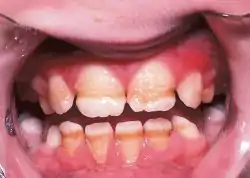

Enamel hypoplasia is a defect of the teeth in which the enamel is deficient in amount,[1] caused by defective enamel matrix formation. Defects are commonly split into one of four categories, pit-form, plane-form, linear-form, and localised enamel hypoplasia.[2][3][4] In many cases the enamel crown has pits or a groove on it, and in extreme cases, sections of the tooth have no enamel, exposing the dentin.[5] Enamel hypoplasia varies substantially among populations and can be used to infer health and behaviour in past populations. Defects have also been found in a variety of non-human animals.[6][7][8]

Enamel hypoplasia is a developmental defect that can affect the primary and permanent teeth in one of two ways. It is sometimes identified as a physically missing tooth structure, and can be seen as pits, grooves or just missing parts in the crown of the tooth.

Therefore, enamel hypoplasia is a defect involving the surface of the enamel associated with a reduced localized thickness of enamel without dentinal exposure. Studies have suggested that enamel hypoplasia, particularly in anterior teeth, is associated with early childhood caries. Hypoplasia in primary anterior teeth is associated with prenatal smoking, excessive weight gain, low birth weight, prematurity and post-natal measles.[17] The random distribution of the round shape of the hypoplastic defects of enamel with hypomineralization, in which there is a continuity of the incremental lines, suggested the possibility that some ameloblasts maintained hypoactivity of their secretory function during their total life span.[18] These changes were confined to the ameloblastic layer. However in severe cases, there was an associated change in the stratum intermedium. They may be submitted as an evidence that enamel hypoplasia is essentially a disturbance in the ameloblasts.[19]